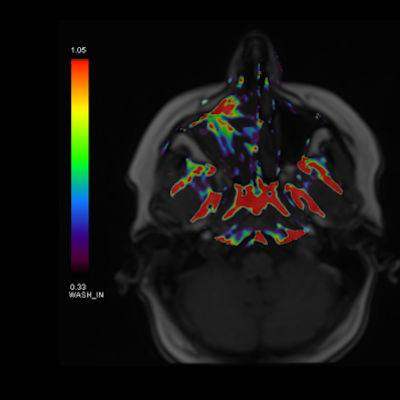

- A) Koronal T2 ağırlıklı görüntülerde sol maksiller sinüs lümenini dolduran, belirgin ‘convoluted’ (karmaşık-kıvrımlı) serebriform patern sergileyen lezyon (oklar), kontrastlı seride heterojen ve yoğun kontrastlanma göstermektedir (oklar). Perfüzyon incelemesinde pedinkülünde perfüzyon artışı gösterdiği, diğer kontrastlanan segmentlerin nispeten hipoperfüze olduğu görülmektedir (ok).

- MR incelemesinde sinonazal inverted papilloma tipik olarak T2 ve post-kontrast T1 serilerde ‘convoluted’ serebriform paternde heterojen sinyal ve kontrastlanma gösteren, pedinküler orijininde daha belirgin perfüzyon artışı sergileyen, genellikle difüzyon kısıtlaması izlenmeyen ve komşu sinüs duvarlarında ekspansiyona bağlı remodelinge yol açabilen benign ancak lokal agresif karakterde bir yumuşak doku kitlesi olarak izlenir.